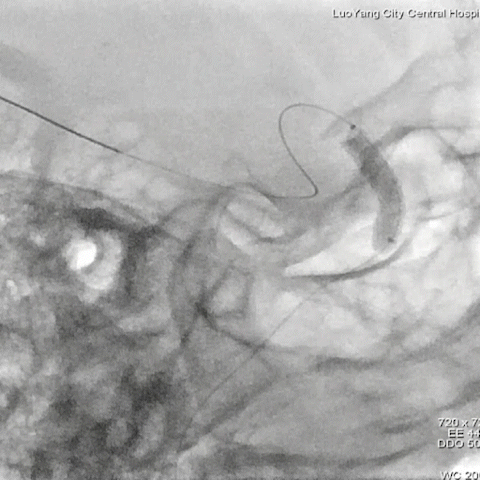

常规消毒铺巾,采用Seldinger 技术穿刺右侧桡动脉。

主动脉弓造影见弓上血管走行III型弓,开口处无明显斑块形成。

Simmons动脉导管同轴输送7F EasyRadial™输送导管至左侧颈内动脉起始段,随后撤出Simmons动脉导管及泥鳅导丝。

路图下,微导丝塑猪尾引导3.5*15mm 颅内球囊扩张导管送至颈内动脉眼动脉段狭窄处,微导丝置于M2段。

颅内球囊扩张导管进行球囊扩张。

球囊泄压后造影。

球囊扩张满意,撤出颅内球囊扩张导管。

输送3.5*15mm 药物涂层支架至眼动脉段。

颅内球囊扩张导管再次进行球囊扩张。

撤出球囊,释放支架。

术后造影示无明显残余狭窄,颅内血管无明显栓塞。